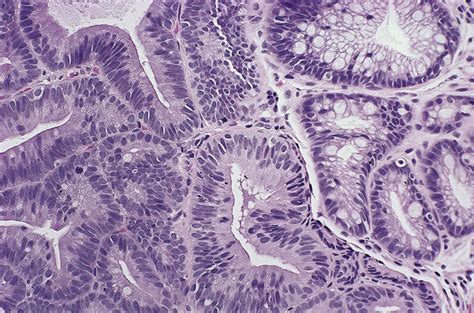

High Grade Dysplasia refers to abnormal changes in the cells lining the esophagus. These changes are more severe than those seen in low-grade dysplasia and indicate a higher risk of developing esophageal cancer. Barrett's esophagus, a condition where the normal cells lining the esophagus are replaced by cells similar to those found in the intestine, is a common precursor to high-grade dysplasia.

• Biopsy: During an endoscopy, tissue samples are taken from the esophagus and examined under a microscope to detect abnormal cells.